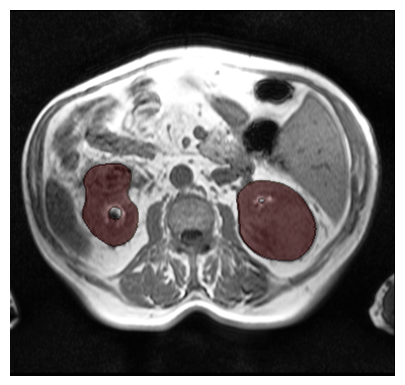

Purpose: To introduce a deep learning model capable of multi-organ segmentation in MRI scans, offering a solution to the current limitations in MRI analysis due to challenges in resolution, standardized intensity values, and variability in sequences. Materials and Methods: he model was trained on 1,200 manually annotated MRI scans from the UK Biobank, 221 in-house MRI scans and 1228 CT scans, leveraging cross-modality transfer learning from CT segmentation models. A human-in-the-loop annotation workflow was employed to efficiently create high-quality segmentations. The model's performance was evaluated on NAKO and the AMOS22 dataset containing 600 and 60 MRI examinations. Dice Similarity Coefficient (DSC) and Hausdorff Distance (HD) was used to assess segmentation accuracy. The model will be open sourced. Results: The model showcased high accuracy in segmenting well-defined organs, achieving Dice Similarity Coefficient (DSC) scores of 0.97 for the right and left lungs, and 0.95 for the heart. It also demonstrated robustness in organs like the liver (DSC: 0.96) and kidneys (DSC: 0.95 left, 0.95 right), which present more variability. However, segmentation of smaller and complex structures such as the portal and splenic veins (DSC: 0.54) and adrenal glands (DSC: 0.65 left, 0.61 right) revealed the need for further model optimization. Conclusion: The proposed model is a robust, tool for accurate segmentation of 40 anatomical structures in MRI and CT images. By leveraging cross-modality learning and interactive annotation, the model achieves strong performance and generalizability across diverse datasets, making it a valuable resource for researchers and clinicians. It is open source and can be downloaded from https://github.com/hhaentze/MRSegmentator.